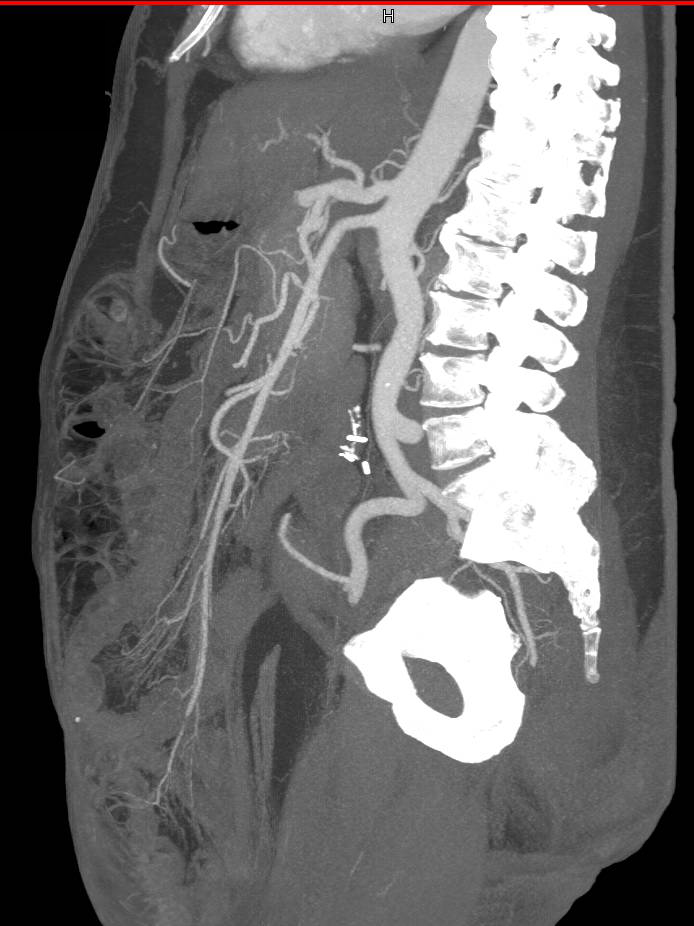

CTS with Peripheral Vascular Disease